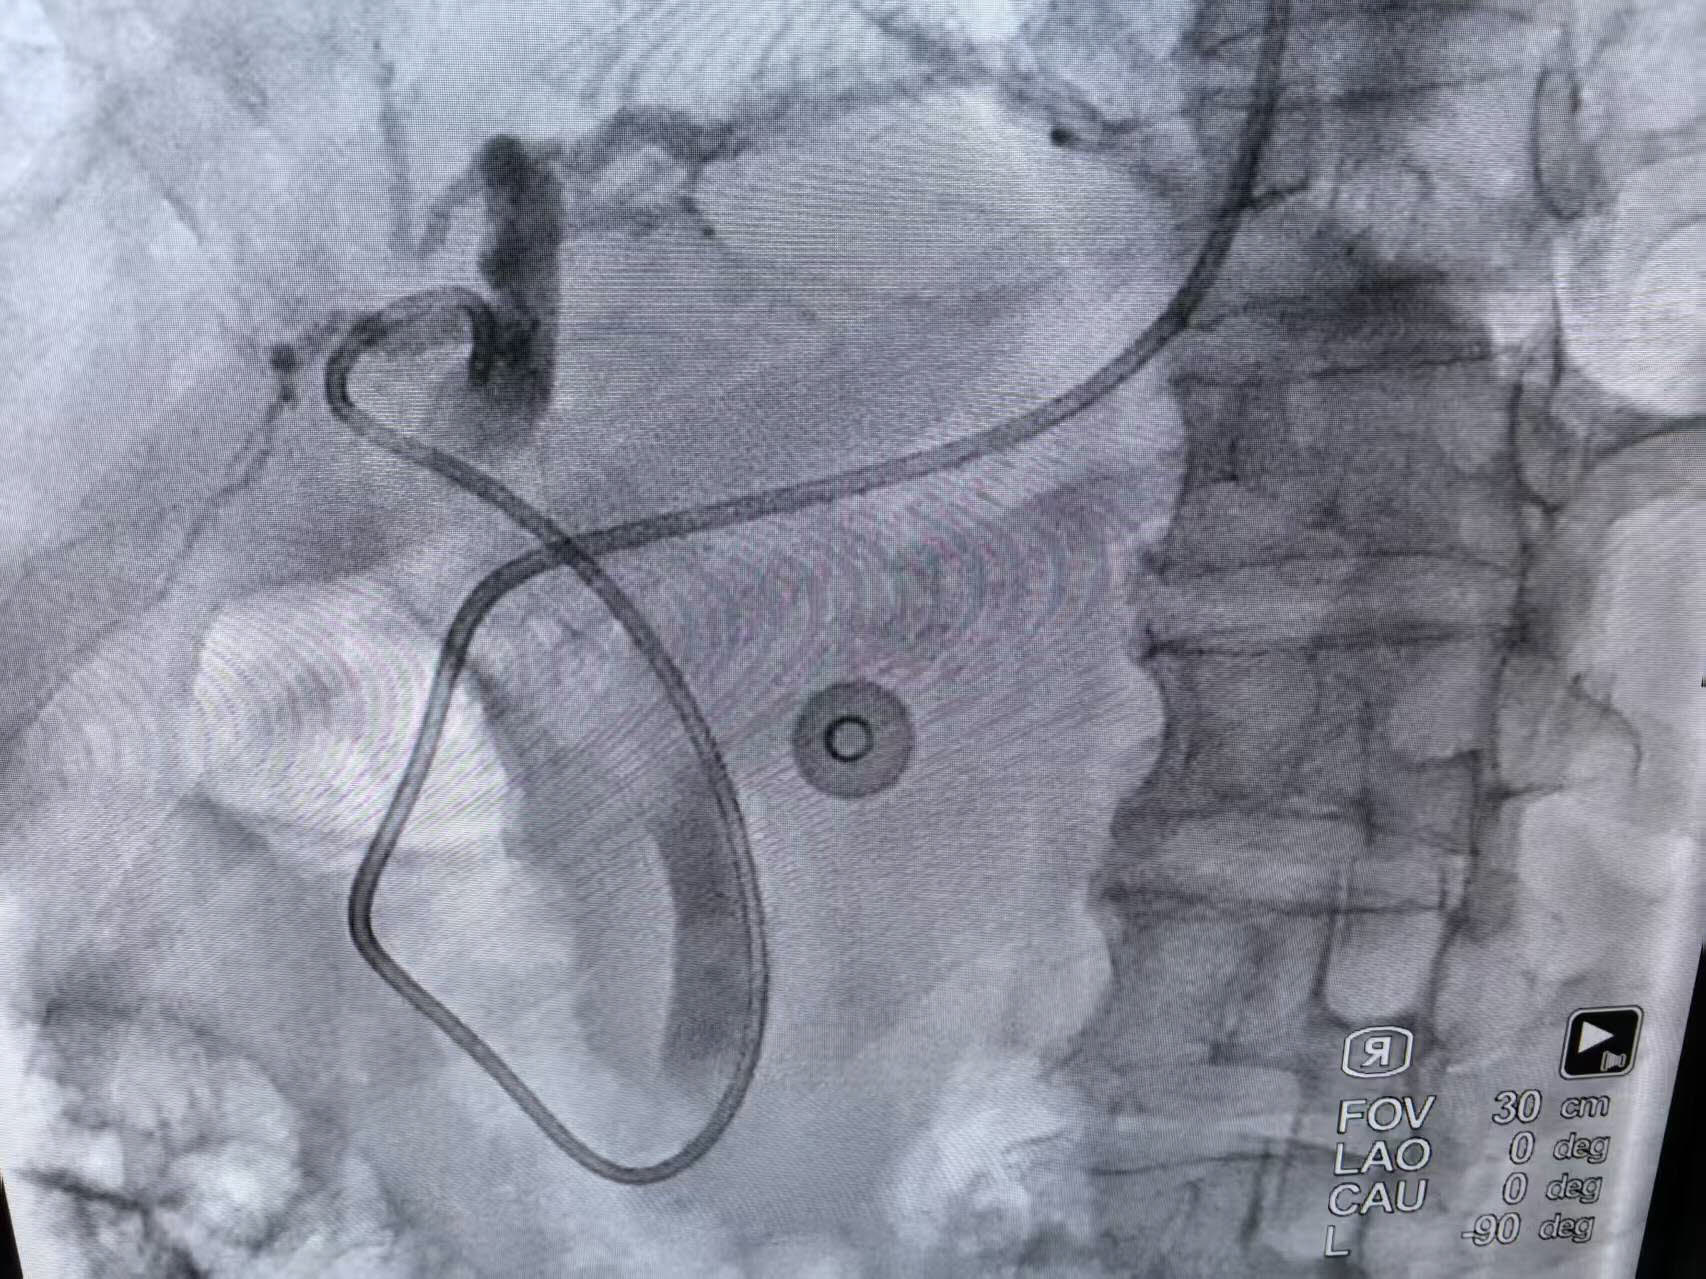

置入胆管引流管

重症胰腺炎合并胆管结石病情凶险,若不及时干预,可能引发感染性休克等致命并发症!医务科组织的多学科会诊迅速启动,消化内科团队凭借精湛技术,通过ERCP(经内镜逆行胰胆管造影术)为患者实施鼻胆管置入术,精准引流胆汁、解除梗阻。